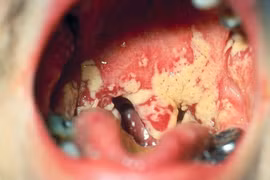

(khoahocdoisong.vn) - Trong giai đoạn thai nghén, sự tăng giảm nội tiết tố đột ngột làm thay đổi độ pH âm đạo, tạo điều kiện thuận lợi cho vi nấm sinh sôi, phát triển và gây bệnh. Mẹ bầu cần điều trị bệnh dứt điểm trước khi sinh con nhằm tránh lây cho bé trong quá trình sinh nở.